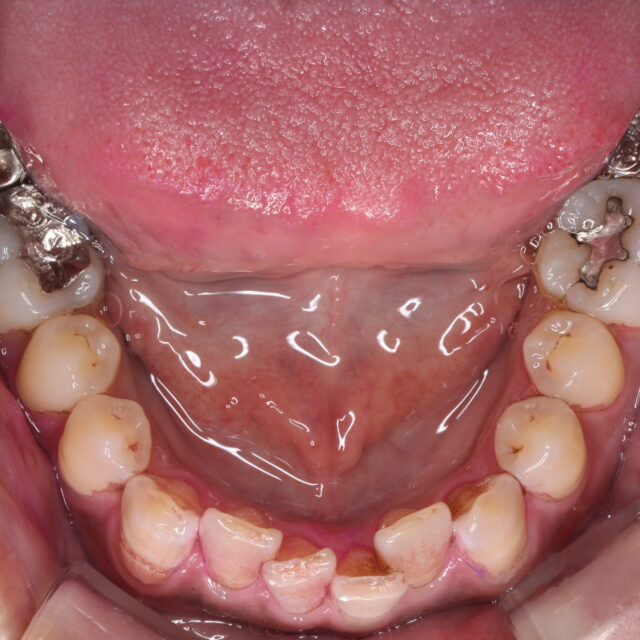

●症例投稿●部分矯正 01 ~下あご前歯編~

- 2022年10月17日

- 咬合治療/フルマウス/咬合再構成,矯正治療